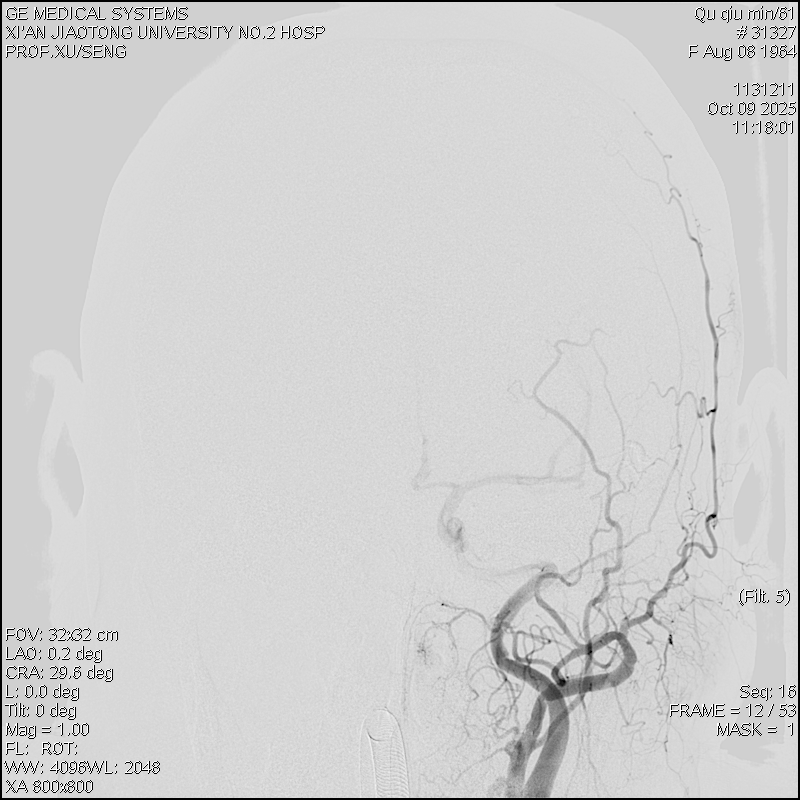

团队结合患者病史、影像学检查以及使用激素后加重的特征,讨论后认为动静脉瘘的可能性较大。但全脊髓造影并未发现硬脊膜动静脉瘘,那么,这个瘘会不会在颅内,只是朝脊髓引流了。根据这个猜测,许刚副主任医师团队为患者进行了全脑血管造影,初步的血管造影并未发现明显病灶。团队并未轻易放弃,又对可疑的各分支血管进行了超选择性造影。最终发现了该患者为脑膜中动脉及枕动脉脑膜支供血的一个非常细小的瘘口。该瘘位于岩骨脊,向下朝脊髓引流,不仔细研究很可能发现不了。

明确诊断后,许刚副主任医师、僧志远主治医师运用介入技术成功对该瘘口进行了栓塞,栓塞术后次日患者的双侧下肢感觉及运动功能就明显好转。一周后患者转当地医院继续康复治疗。

术前颈外造影正位

术前颈外造影侧位